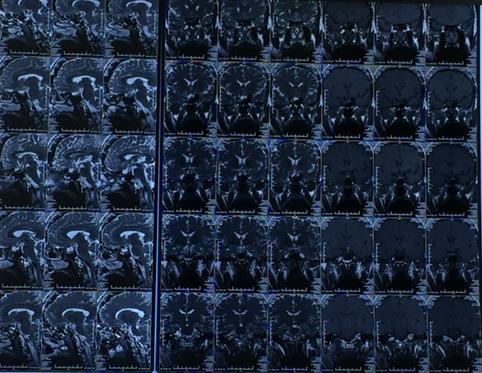

术前影像学检查: